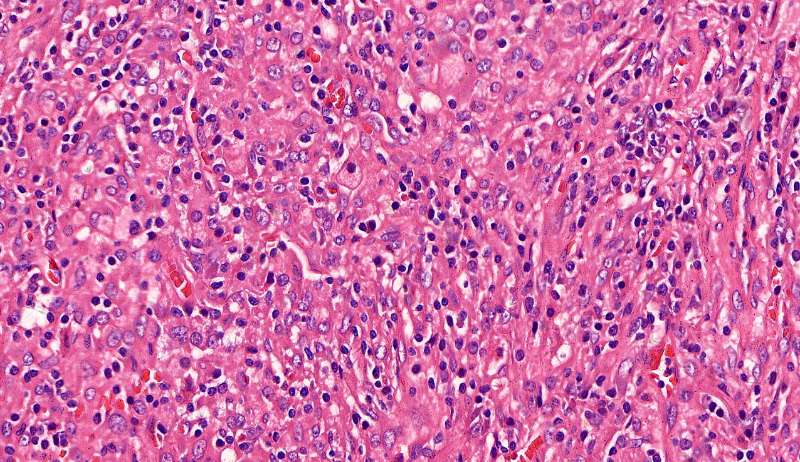

最后发一例化脓性炎症

中性粒细胞很多,此处组织结构破坏

左侧液化,脓肿壁较规则平滑

周围的炎症机化区

破坏力在这里逐渐减弱

逐渐从中性粒细胞转为淋巴细胞为主

周边区:

肺泡内有渗出,逐渐吸收 机化是不是纤维细胞增多看的?王:是的